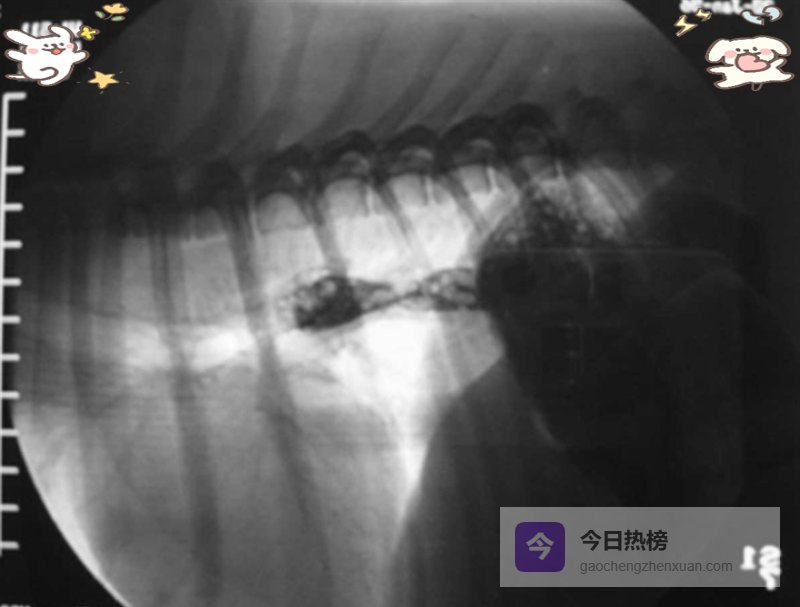

食管炎若反复发作,会形成自我延续的恶性循环:LES压力下降→反流频率增加→炎症加重→LES进一步松弛。长期后果包括食管狭窄(图8)及鳞状细胞癌风险升高。人类巴雷特食管已被证实为癌前病变;猫虽少见肠化生,但慢性反流与肿瘤之间是否存在关联,值得长期追踪观察。

图8. 食管狭窄犬的钡剂造影